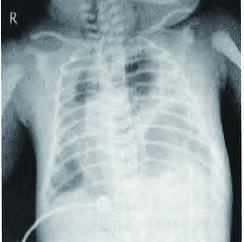

1 资料与方法患儿,男,胎龄39周,体质量3.75 kg,产前诊断左侧先天性膈疝。本例患儿在妇产科医院出生,5 min Apgar评分7分,之后气促,发绀不断加重,予以气管插管,常频通气6 h后改高频通气,12 h后出现右侧气胸,缺氧加重,见图 1,置胸腔引流管排气后,状况仍不见改善,14 h后紧急呼叫本院ECMO团队会诊。患儿采取高频通气模式,频率9Hz,氧浓度100%,在多巴胺10ug/(kg•min)、多巴酚丁胺10 μg/(kg•min)、肾上腺素0.4 μg/(kg•min)、米力农0.5 μg/(kg•min)支持下血压45/32 mmHg,心率173次/min,查血气pH值7.334, PaO2 37.1mmHg,PaCO2 34.5 mmHg,SaO2 74.2%,乳酸2.5 mmol/L,PaO2/FiO2为37。明确诊断:CDH并发严重缺氧性呼吸衰竭。排除颅内出血、心内严重畸形,符合ECMO适应证,于出生18 h,在妇产科医院建立静脉一动脉ECMO(VA-ECMO),切开右颈内静脉及右颈总动脉置入插管(美国美敦力,Fr12,Fr10),膜肺选用米道斯800型套包,离心泵选用MAQUET RF-32,ECMO流量维持在0.25 L/min,之后低氧血症立即改善。

| 图 1 左侧先天性膈疝伴右侧气胸,高频通气中 |